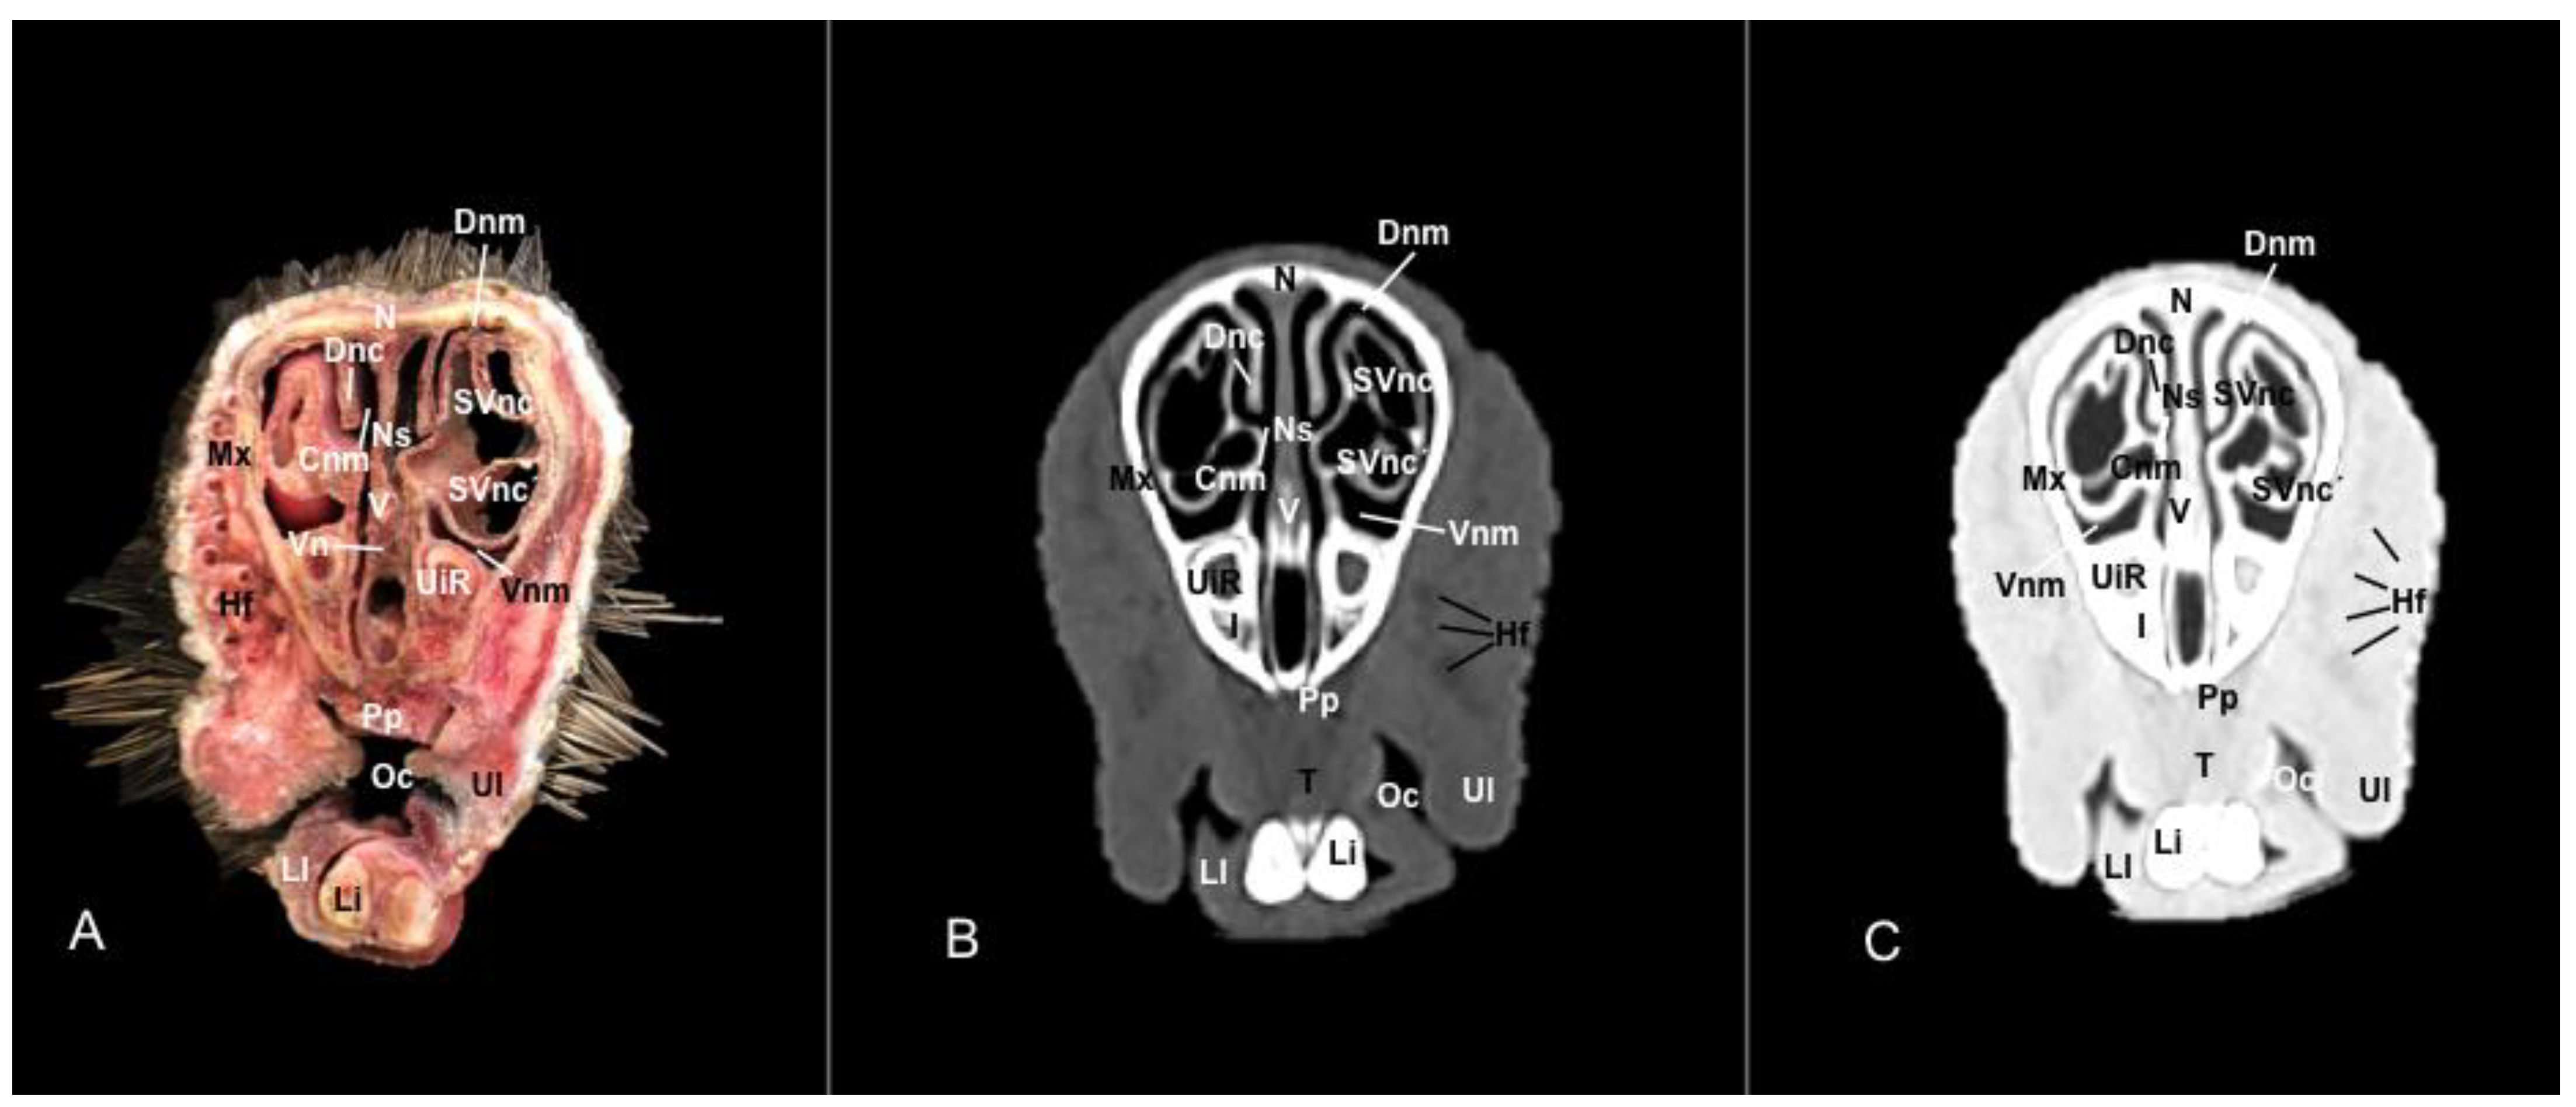

3.1. Anatomical Sections

3.2. Computed Tomography (CT)